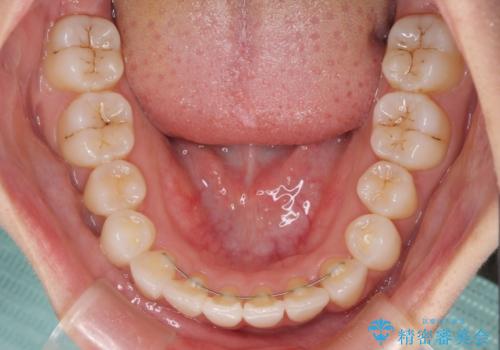

インプラント治療は当初の狙い通り、矯正治療期間中に行い、スムーズに処置を進めることができました。

歯並びが整ったことで治療前に認められた歯肉炎は全くなくなり、患者様には大変満足していただきました。